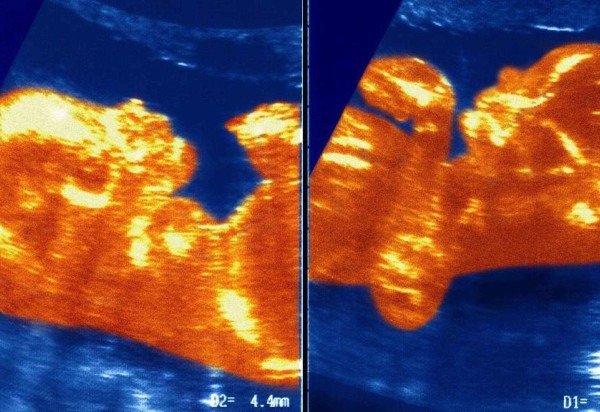

Os pesquisadores suspeitam que, durante a gestação, a placenta de cada um dos gêmeos — Ana Paula e o irmão — teve algum tipo de contato e isso formou uma conexão de vasos sanguíneos que levou sangue do menino para a menina.

Com isso, as células sanguíneas do irmão de Ana Paula recolonizaram a medula óssea dela, que passou a produzir células sanguíneas com cromossomos XY, enquanto o resto do corpo dela seguiu XX mesmo.

"Houve um processo de transfusão que a gente chama de transfusão feto fetal. Em algum momento, houve um entralaçamento das veias e artérias dos dois ali no cordão umbilical. E ele passou todo o material dele pra ela, de sangue. E o mais impressionante é que esse material permaneceu a vida inteira ali", explica Maciel.